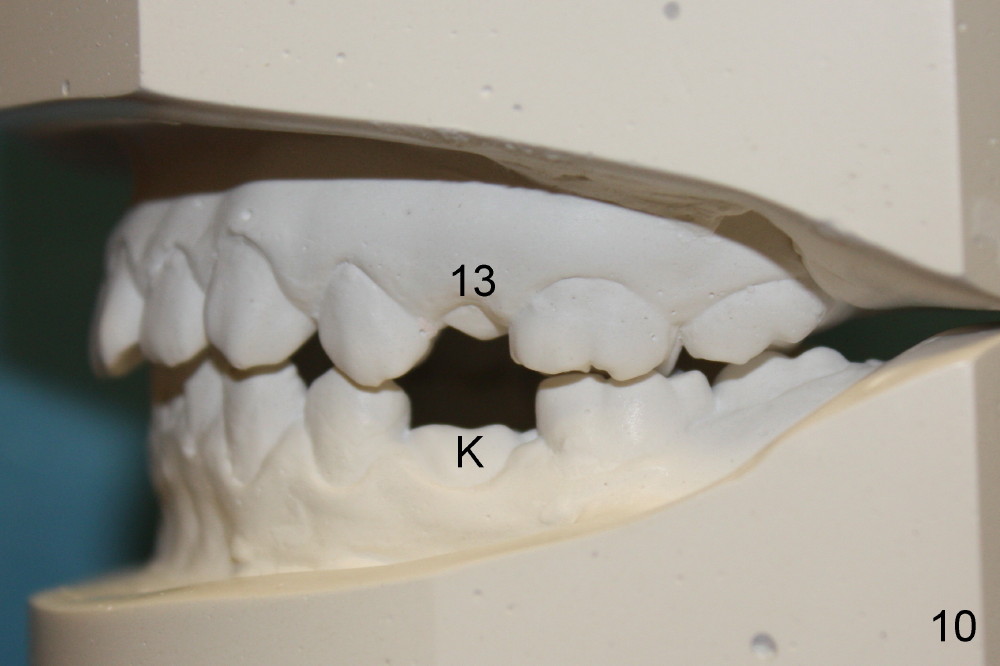

A 13-year-old Asian girl seeks orthodontic treatment for crowding. The lower 2nd bicuspids are congenitally missing (Fig.1,8), whereas the upper right one rotates 180° and the upper left is partially impacted (Fig. 1, 7). The lip muscles strain when the lips close (Fig.3). Orthodontic treatment started with extraction of four affected teeth (#4,13, K and T) 6 months ago. .018' niti wires are being used. Dental midlines do not coincide preop and intraop (Fig.4,4'). Pre-op front view shows that the upper dental midline coincides with the facial one (Fig.1'). There is Class I canine and molar relationship on the right (Fig.5,5',9,9'); open bite on the left (Fig.6,6',10,10').

Next steps: 1. Use elastics to close open bite on the left and to upright #31 (linguoversion, probably #18 to lesser degree) (Fig.8,8',9,9'); 2. Shift the lower midline to the left before closing 2nd bicuspid spaces. What is the best way to close spaces? Power chains for both arches or closed coil springs for upper and loop for lower (which is used for Tiffany Yue)? Since intraop profile is acceptable (Fig.2',3', as compared to Fig.2,3 (preop)), molars will be mesialized.

Update: The left open bite was closed less than one month by wearing elastics between upper and lower teeth (Fig. 6'''). The occlusal plane and midline improve (Fig.4''). Wires have gradually changed to .016x.016, .016x.022 and now .018x.025 with power chains. All the spaces are closed except the one in LR (Fig.7''-10''). What I cannot accomplish is to fix meisal (Fig.5'' (white line), 9'') and lingual (Fig.8'' arrows) inclination of LR molars, although elastic is instructed to be placed between UR7 buccal and LR7 lingual. The rectangular wires could be twisted to fix lingual inclination. Which should be done first: LR space or LR molar inclination? Click each figure for magnification.